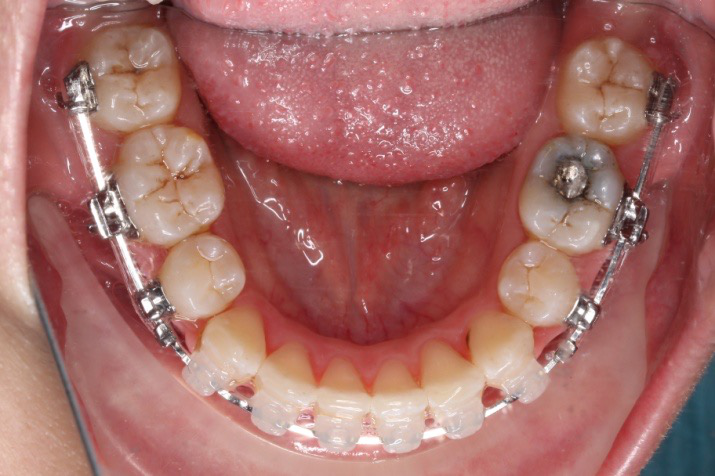

2018.11.14  术后磨牙尖牙I类关系,中线齐,覆合,覆盖正常

牙根基本平行,未见牙根吸收

10 M after Post-Tx

10 M after Post-Tr

2019.08.06  术后  10个月复查